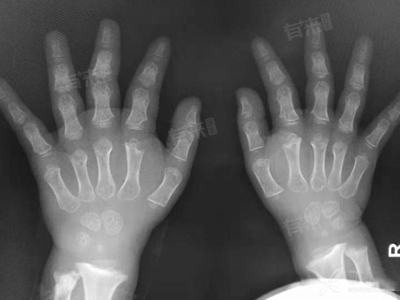

在进行关节松动术之前,需要进行全面的检查。首先是体格检查,医生会检查关节的外观,查看是否有红肿、畸形等情况,同时检查关节的活动度,确定关节活动受限的程度和方向。血液检查方面,可能会检测炎症指标,如血沉、C-反应蛋白等,以判断关节是否存在炎症。影像学检查是重要的部分,X线可以观察关节的骨骼结构,查看是否有骨折、骨质增生等情况。